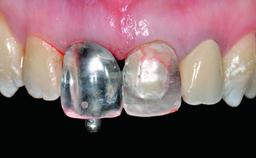

Replacement of a Missing Upper Left Central Incisor: Late Placement of an RC Bone Level Implant, CAD/CAM Zirconia Abutment

Eduardo R Lorenzana, Jason R Gillespie

A healthy 37-year-old female patient was referred for a consultation on the replacement of missing tooth 21 with an implant-supported restoration. She stated that several years previously the tooth had been traumatically avulsed following a motor vehicle accident. The tooth was replaced with a three-unit fixed partial denture (FPD) immediately afterwards. Over time, she became disillusioned with the FPD and looked for a different option, including orthodontic therapy. She presented still in her orthodontic appliances, with the pontic sectioned free from the FPD but attached to the archwire. Her orthodontist felt that orthodontic treatment had been successfully completed, but nevertheless referred her before removing the appliances in case adjustments were necessary.